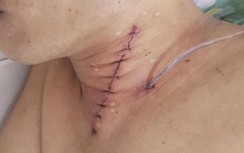

Sau hội chẩn, các bác sĩ thống nhất phương án mở khí quản cấp cứu dưới vị trí dị vật để giải phóng đường thở mà không tiến hành đặt nội khí quản như bệnh nhân suy hô hấp vẫn hay thường được làm vì nguy cơ đẩy sâu dị vật vào đường thở phía dưới, sau đó sẽ gây mê tiến hành gắp dị vật qua đường hô hấp.

Tuy nhiên, dưới nội soi phế quản dị vật kích thước lớn, rắn, bề mặt trơn nhẵn không thể lấy được với dụng cụ nội soi phế quản. Các bác sĩ tiếp tục hội chẩn tiến hành phương án gắp dị vật qua đường miệng dưới gây mê.

Sau lấy dị vật, bệnh nhân tỉnh táo, dễ chịu, được chuyển về Khoa Tai mũi họng theo dõi tiếp.